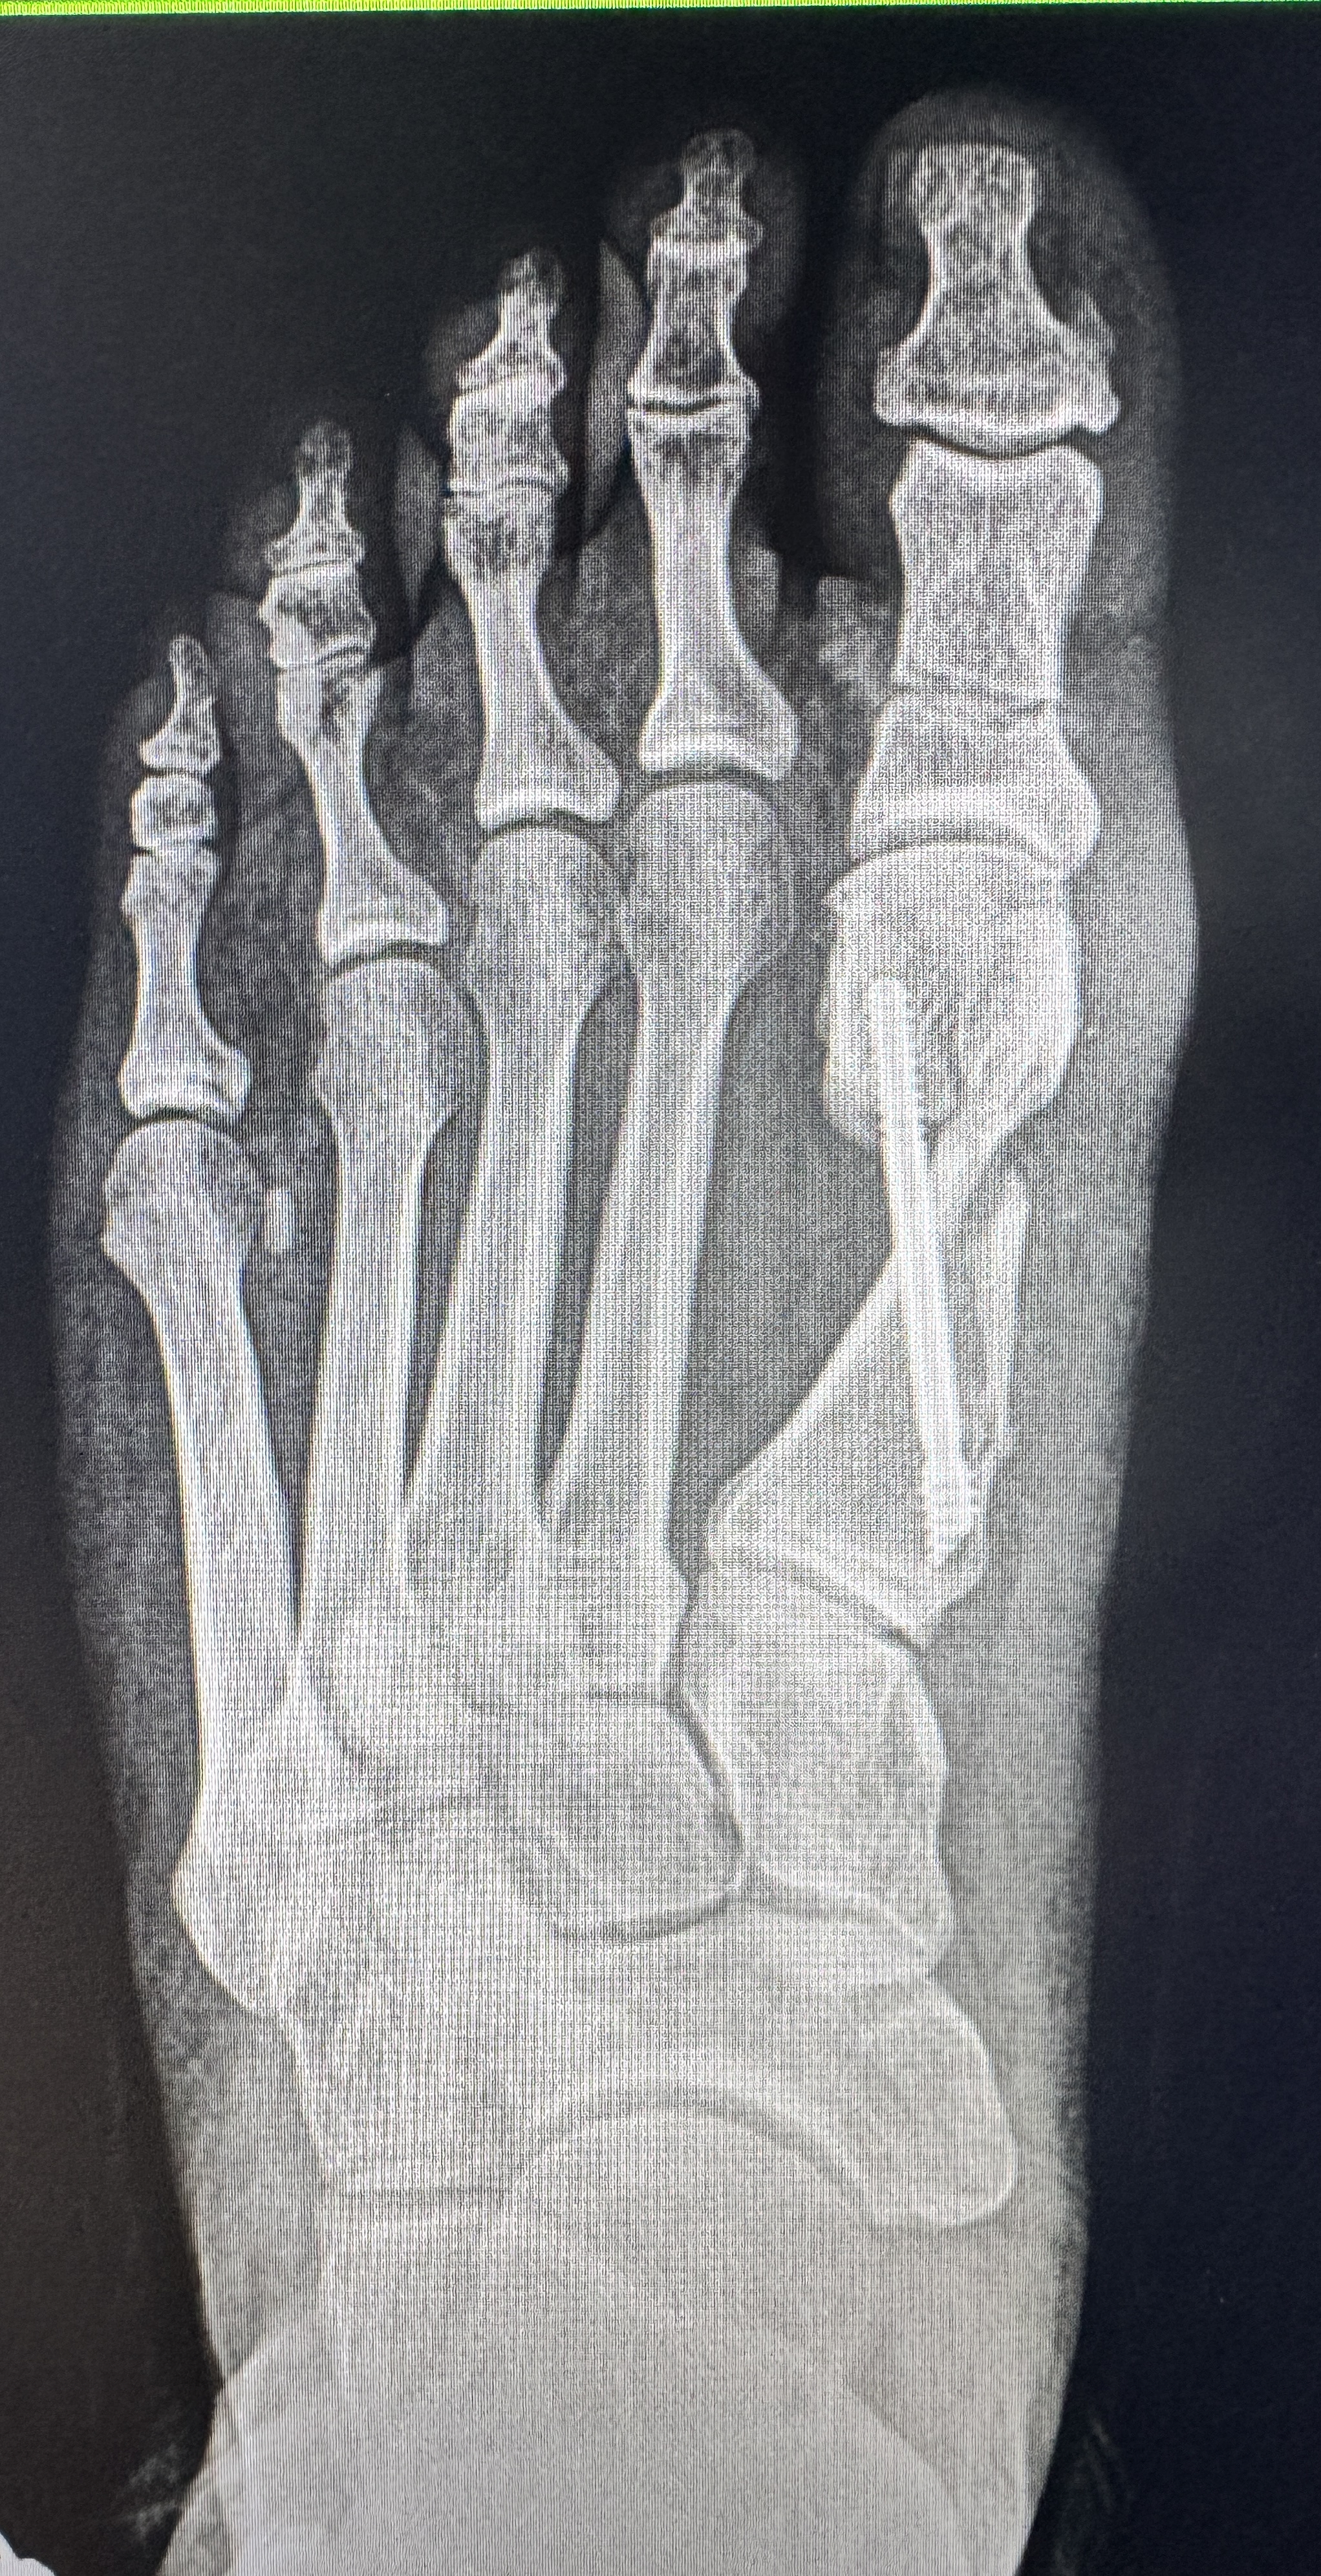

Significant hallux valgus deformity with lateral toe crowding

Excellent realignment — fixation hardware placed through minimal incisions

The following X-rays and clinical photos are from Dr. Bregman's own patients. Note the dramatic bone realignment on X-ray — and on the clinical photos, the incisions are so small they are almost invisible.